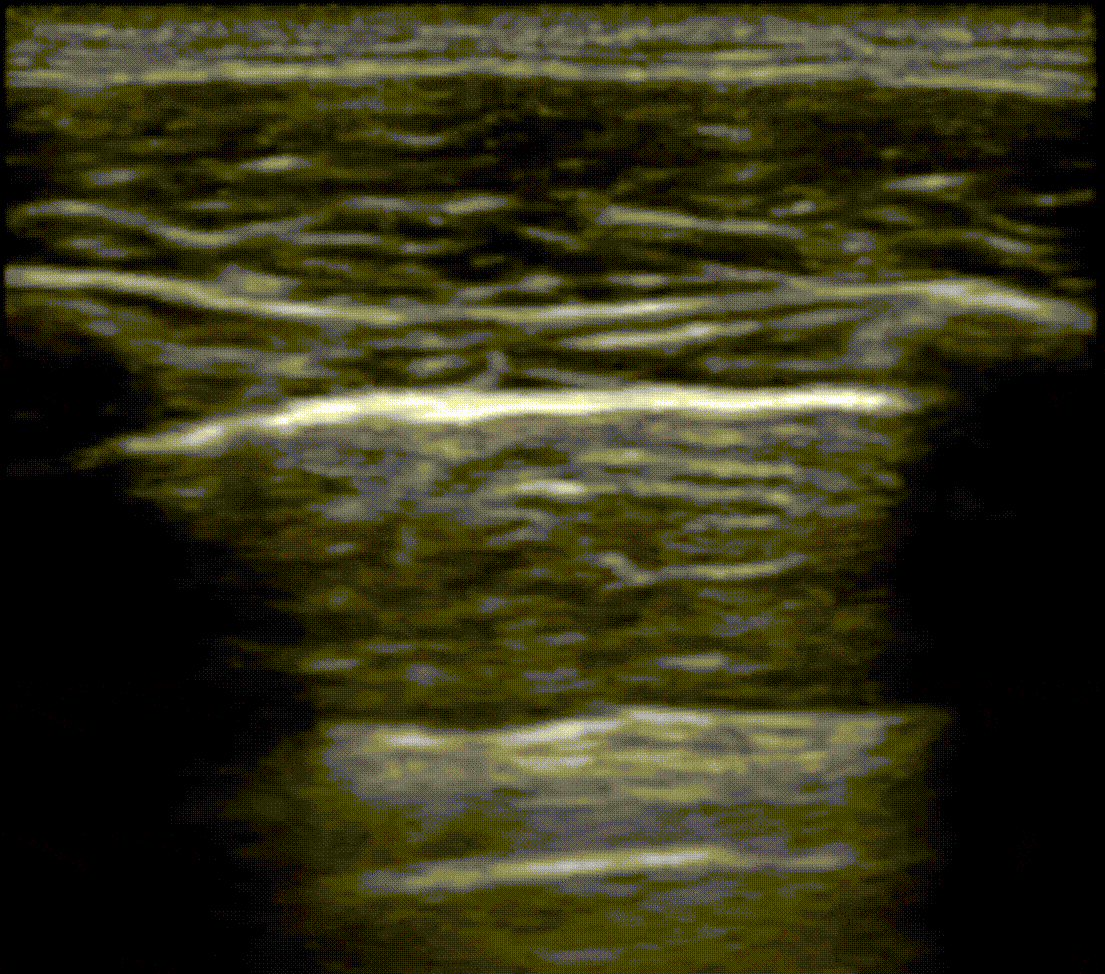

View US images that rule in or rule out a pnuemothorax